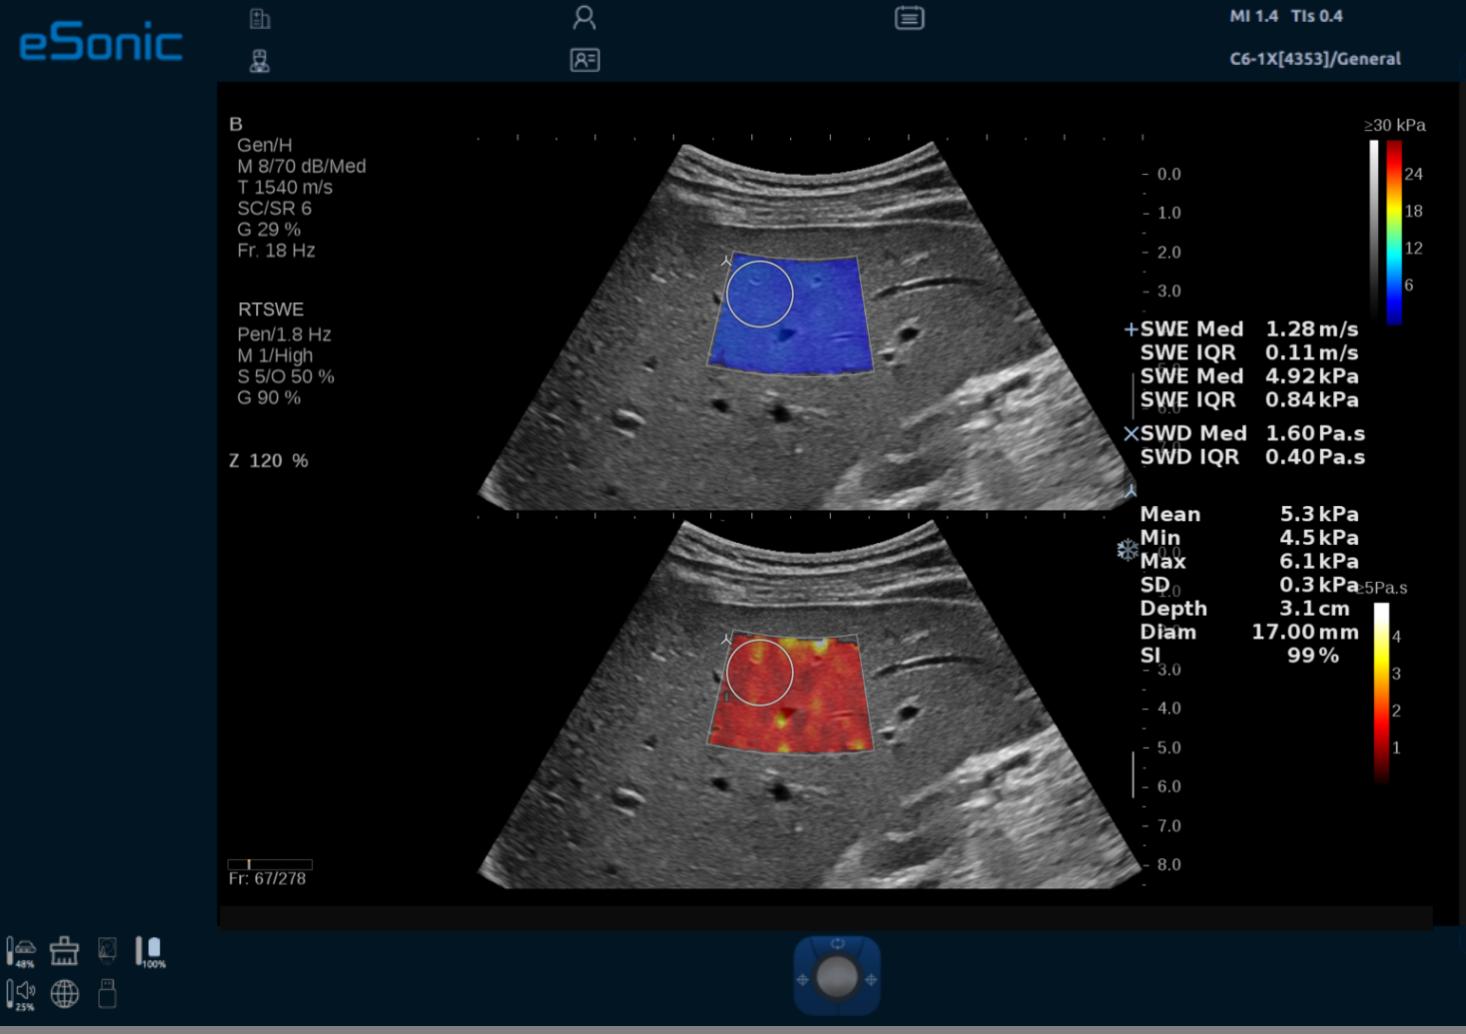

3D RTSWE 三维剪切波硬度定量成像

eTriplex 弹性三同步成像

QVisco 粘弹性定量成像